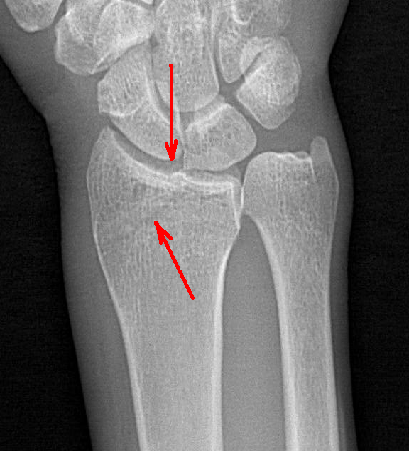

隱匿性骨折高清圖像

其次,動(dòng)態(tài)DR 空間分辨率高,圖像清晰,診斷準(zhǔn)確率高,且具有視頻保存、回放功能,可以完整的記錄整個(gè)透視動(dòng)態(tài)圖像,便于重復(fù)觀察、分析,減少遺漏。相對(duì)于傳統(tǒng) X 線檢查,動(dòng)態(tài)DR輻射量較小,可有效減少 X 線所造成的輻射,呵護(hù)醫(yī)患健康。